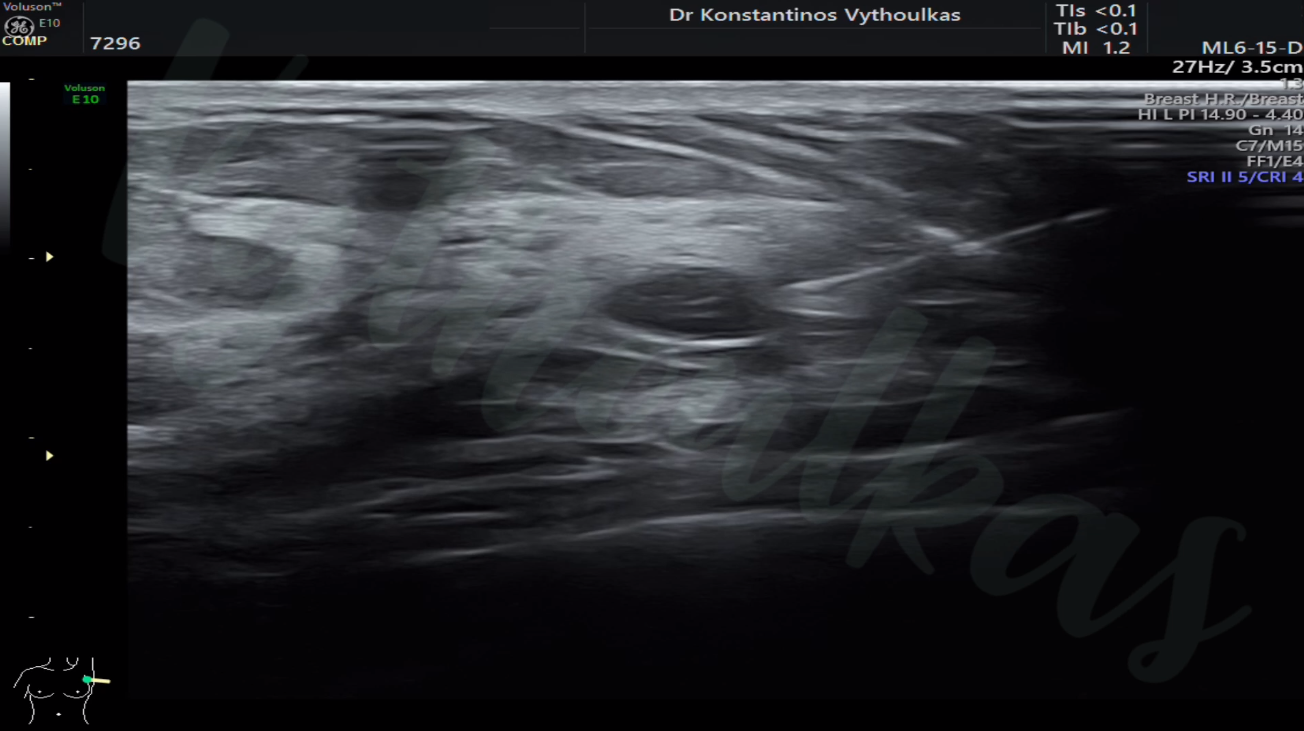

Για την ορθή διάγνωση ενδεχόμενων παθήσεων, στο ιατρείο εκτελούνται:

- Ψηλάφηση

- Υπερηχογράφημα

- Ελαστογραφία

- Παρακέντηση για Κυτταρολογική Εξέταση (Fnac)

- Core Biopsy

- Ο υπερηχογραφικός έλεγχος των μαστών γίνεται, κυρίως, για διαγνωστικούς λόγους μετά από ύποπτο απεικονιστικό ή κλινικό εύρημα.